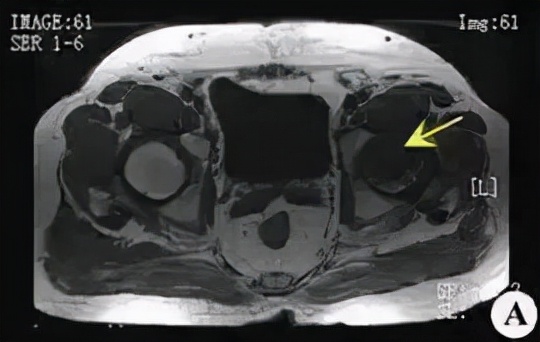

磁共振: 是一种有效的非创伤性的早期诊断方法。

大多表现为股骨头前上部异常信号:T1为条带状低信号;T2为低信号或内高外低两条并行信号影,即双线征(double line sign)。双线征中外侧低信号带为增生硬化骨质,内侧高信号带为肉芽纤维组织修复所致。